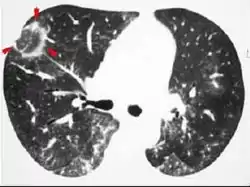

The chest x-ray is distinctive with features that appear similar to an extensive pneumonia, with both lungs showing widespread white patches. The white patches may seem to migrate from one area of the lung to another as the disease persists or progresses. Computed tomography (CT) may be used to confirm the diagnosis. Often the findings are typical enough to allow the doctor to make a diagnosis without ordering additional tests.[18] To confirm the diagnosis, a doctor may perform a lung biopsy using a bronchoscope. Many times, a larger specimen is needed and must be removed surgically.

Plain chest radiography shows normal lung volumes, with characteristic patchy unilateral or bilateral consolidation. Small nodular opacities occur in up to 50% of patients and large nodules in 15%. On high resolution computed tomography, airspace consolidation with air bronchograms is present in more than 90% of patients, often with a lower zone predominance. A subpleural or peribronchiolar distribution is noted in up to 50% of patients. Ground glass appearance or hazy opacities associated with the consolidation are detected in most patients.

Unusual presentations of organizing pneumonia

While patchy bilateral disease is typical, there are unusual variants of organizing pneumonia where it may appear as multiple nodules or masses. One rare presentation, focal organizing pneumonia, may be indistinguishable from lung cancer based on imaging alone, requiring biopsy or surgical resection to make the diagnosis.[19]